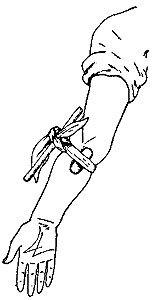

112 Surface Veins and Deep-Lying Arteries of Inner Side of Right Arm and Hand

321 A Tourniquet